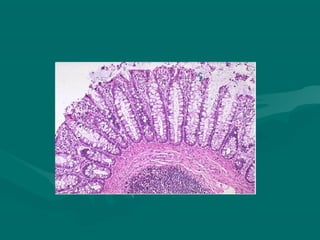

TECIDO EPITELIAL

Revestimento de partes internas ( mucosas) e

externas (pele);

Tecido epitelial e tecido conjuntivo